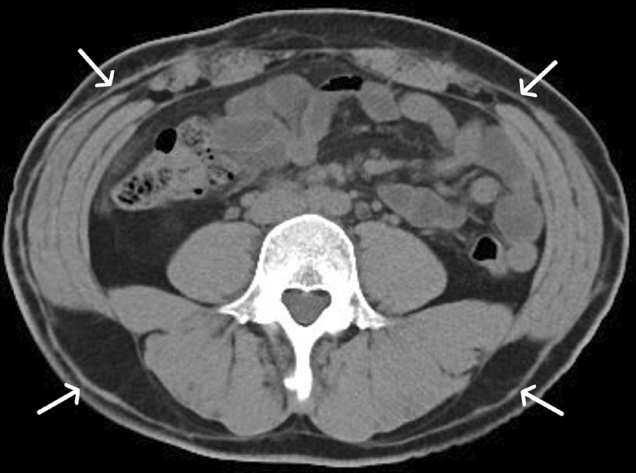

Hidradenitis suppurativa

Hidradenitis suppurativa (HS) is a chronic inflammatory skin disease involving the folliculopilosebaceous units and apocrine sweat glands and is also known as acne inversa. It has a female predominance and is associated with obesity, smoking, Crohn’s disease, and Dowling Degos disease and may be complicated by chronic sinus and fistula formation, epidural abscess from deep extension, osteomyelitis, and squamous cell carcinoma developing in chronic inflammatory tracts [41–43].

The disease typically affects apocrine gland-rich areas of the body, such as the genitofemoral area and axillae [42]. Imaging shows marked thickening of the skin, edema of the subcutaneous tissues, and formation of multiple small subcutaneous abscesses as well as sinus and fistula formation. It has a characteristic distribution, causing severe skin thickening which is typically bilateral and fairly symmetric along the perineum and gluteal folds (Fig. 21) or the axillary folds [44]. By comparison, simple cellulitis tends to have a more diffuse “fat stranding” appearance with more mild skin thickening. The involved areas are typically of soft tissue attenuation on CT, dark on T1, and bright on T2-weighted MR images with peripheral enhancement of subcutaneous abscesses (Fig. 22). MR imaging can be very helpful when HS involves the genitofemoral areas in patients with Crohn’s disease (who have an increased incidence of HS) to determine the cause of a peri-anal fistula, which can occur in both Crohn’s disease and HS. A recent study showed that while some MRI features of anoperineal disease may overlap between Crohn’s disease and HS, a specific diagnosis of HS is possible with a combination of three features: absence of perianal predominance of disease, absence of rectal wall thickening, and bilaterality of features [45].

Fig. 21.

30-year-old male with Hidradenitis Suppurativa (HS). Axial (a, b) and coronal (c) CT reformats through the gluteal cleft and perineum demonstrate nodular, bilateral, fairly symmetrical subcutaneous soft tissue thickening (arrows) with sinus track formation (arrowhead) in a patient with pathologically proven HS. Contrast these findings with a different patient with cellulitis. Axial (d) CT image illustrates diffuse “fat stranding” in the left greater than right gluteal subcutaneous soft tissues (curved arrows), compatible with cellulitis. A developing fluid collection is noted in the right gluteal subcutaneous tissues